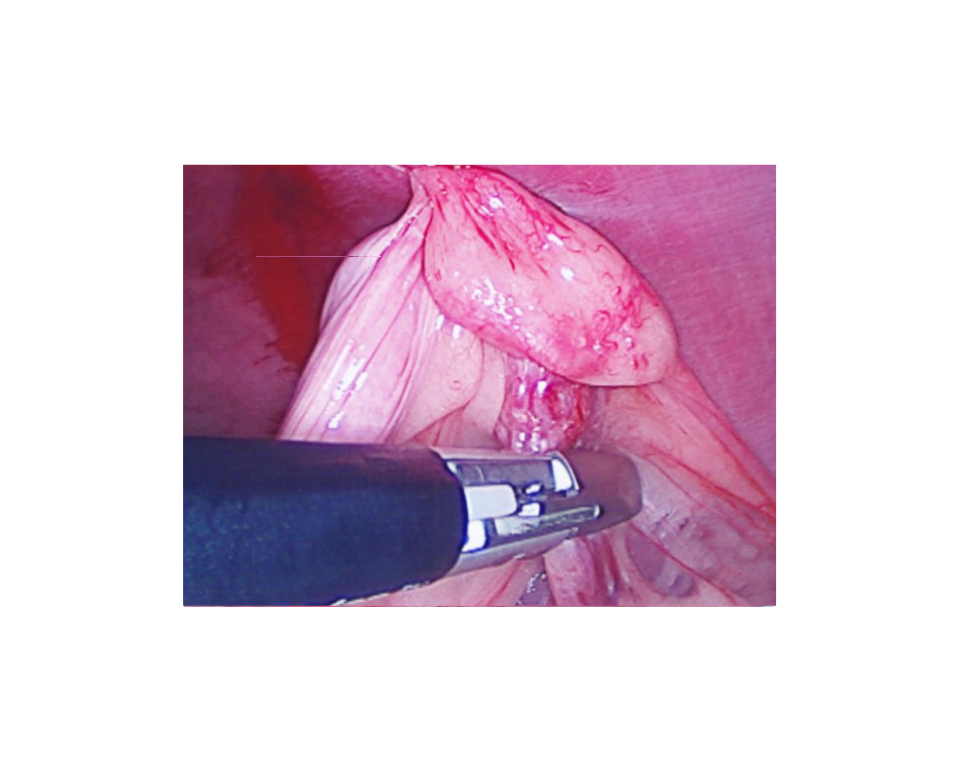

A blood vessel sealing device (LigaSure) is used to seal and divide the tissues and blood vessels from the body: